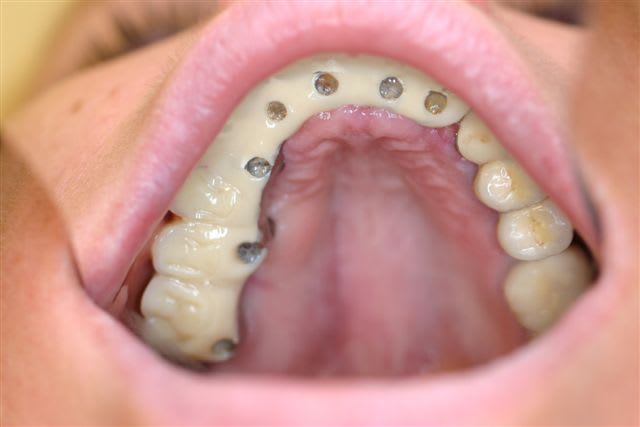

Voici le modèle stéréolithographique et la apno post op

Pépé